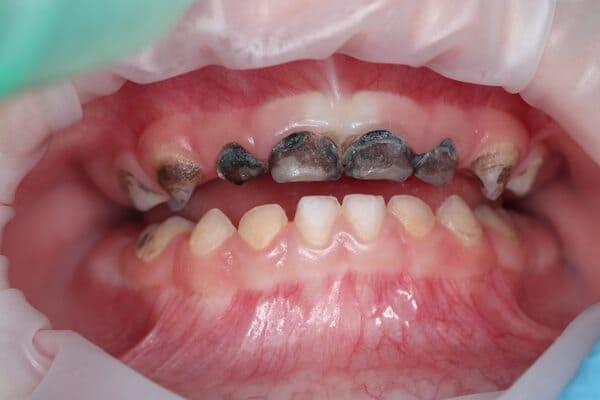

Пацієнт 2 років, уражено десять зубів, шість із яких потребують покриття коронками. В зв’язку зі значним об’ємом та складністю лікування прийнято рішення про лікування в умовах анестезіологічного забезпечення. Раніше була спроба пролікувати ці зуби застарілими методами, які не тільки не є ефективними відносно лікування, а ще і додають дитині комплексів через характерне фарбування зубів. Через високи естетичні вимоги дитини і батьків було прийнято рішення покривати естетичними цирконієвими коронками, як передні так і бічні зуби. Через 2,5 години дитина без інфекції в порожнині рота, з відновленим здоров’ям та естетикою посмішки може кусати, жувати, посміхатись без болю та дискомфорту. Останнє фото через 2 роки після лікування, оскільки естетичні коронки в дитячій стоматології - це надійність, естетика та функція.